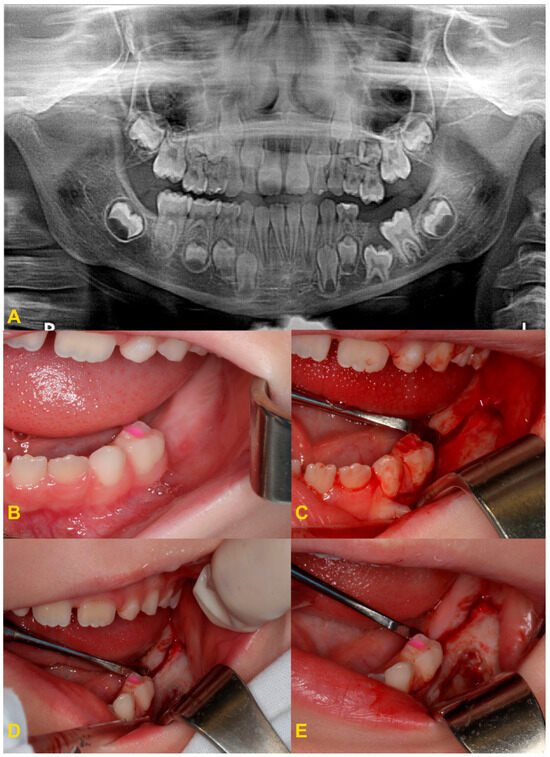

The diagnosis of tooth infraocclusion is multifaceted, involving a combination of detailed medical history, clinical examination, and advanced imaging techniques. To extend the diagnosis and monitor the reinclusion process, radiological examinations (dental X-rays—Figure 2, panoramic X-rays—Figure 3, and cone-beam computed tomography (CBCT)—Figure 4), diagnostic models (Figure 5A,B), intraoral scans (Figure 5C,D), and dental photography (Figure 6, Figure 7, Figure 8, Figure 9 and Figure 10) are used.

Figure 2.

Radiological imaging—dental X-ray of teeth nos.: (A) 84, (B) 74, and (C) 74.

Figure 3.

Panoramic X-ray examinations: (A) mild infraocclusion of tooth no. 55 (immersion of 1–2 mm); (B) moderate infraocclusion of tooth no. 55 (infraposition of 2–3 mm), displacement and growth delay of permanent successor, and angulation of the adjacent teeth with loss of space; and (C) severe infraocclusion of tooth no. 75 (immersion of more than 3 mm), displacement and growth delay of permanent successor, severe angulation of the adjacent teeth with loss of space (the same patient as in Figure 6C).